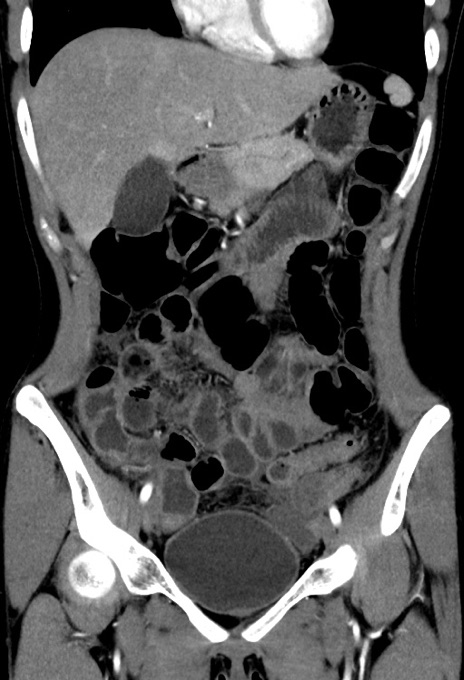

症例17(冠状断像)

【症例】20歳代女性

【主訴】嘔吐、下腹部痛

【現病歴】昨日夕食後に嘔吐し下腹部痛が出現。本日になっても嘔吐持続し改善しないため来院。

【身体所見】意識清明、BT 37.2℃、BP 108/67mmHg、腹部:平坦、やや硬、下腹部正中から右にかけて圧痛あり、反跳痛軽度あり、tapping pain(+)。

【データ】WBC 13600、CRP 14.94